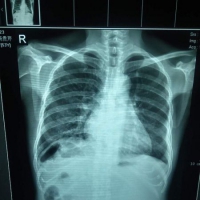

• 请各位老师给看看这张片子。